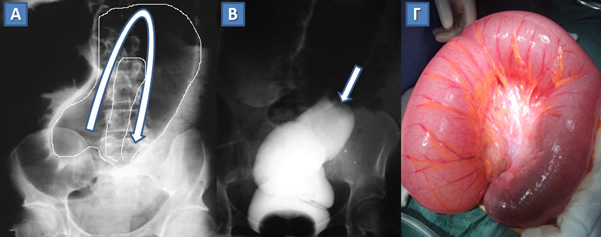

Συστροφή σιγμοειδούς.

Α. Απλή ακτινογραφία κοιλίας με εικόνα ανεστραμμένου U (βέλος), που αντιστοιχεί στο πλήρες αέρα συστραμμένο σιγμοειδές (περιγεγραμμένο με λευκή γραμμή).

Β. Υποκλυσμός με γαστρογραφίνη, όπου η προώθηση του σκιαγραφικού διακόπτεται στη θέση της απόφραξης που προκαλεί η συστροφή (βέλος).

Γ. Διεγχειρητική εικόνα.

(Από το προσωπικό αρχείο του Γ. Θεοδωρόπουλου)